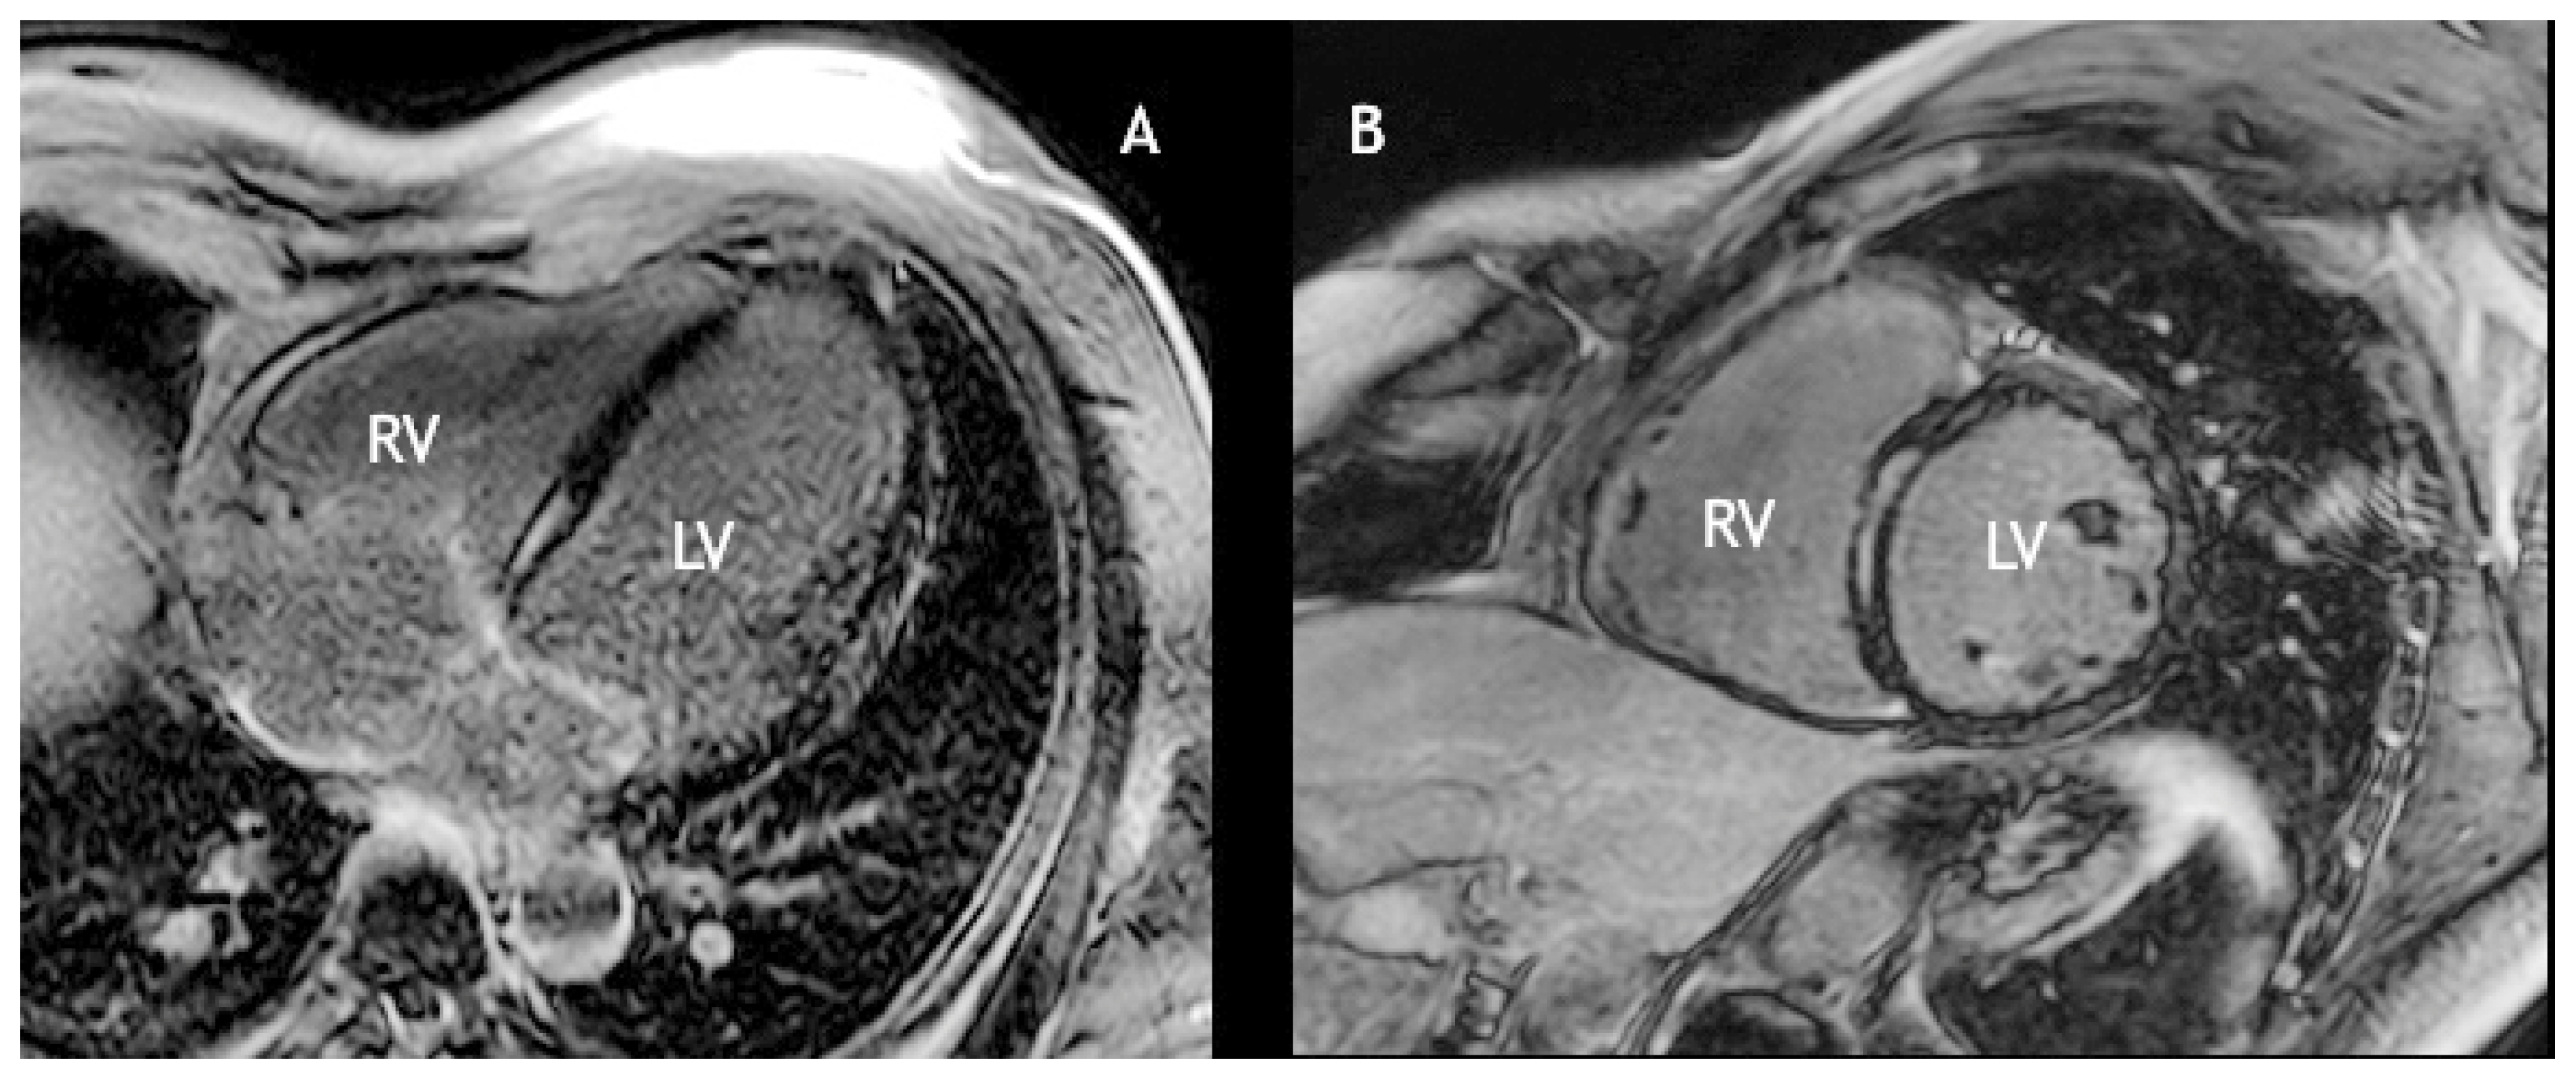

Case report